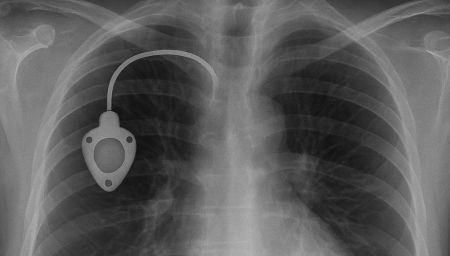

항암관(Chemoport)삽입

Chemoport는 항암제처럼 자극이 강한 약물을 안전하고 안정적으로 투여하기 위해 흉부 피부 아래에 이식하는 중심정맥 사용 포트입니다. 팔 혈관이 약하거나 반복 주사로 인한 통증이 걱정되는 환자에게 도움을 줄 수 있으며, 장기간 치료가 필요한 경우 편안하게 항암 치료를 지속할 수 있도록 설계되어 있습니다.

항암관(Chemoport)삽입 과정

01

국소마취 후 작은 절개를 시행 (보통 쇄골 아래 약 2~3cm 정도 절개)

02

정맥에 카테터 삽입 후 포트와 연결

03

방사선으로 카테터 위치 확인

04

피부 봉합 후 소독 드레싱